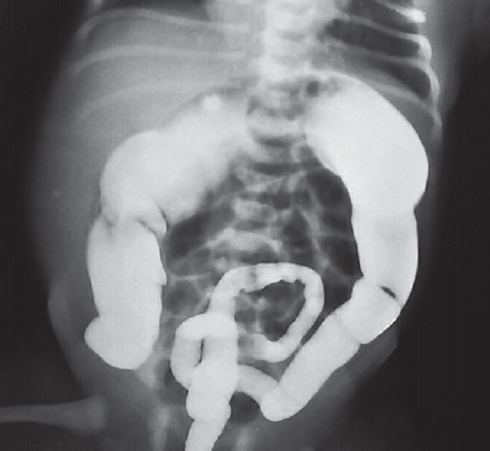

Hirschsprung’s disease usually manifests from the first days of life and is diagnosed in the newborn period. In some patients Hirschsprung’s disease can’t be diagnosed in the newborn period because of different forms of disease and clinical features. From 2008 to 2019 75 patients with Hirschsprung’s disease were operated in the City Children’s Hospital No. 1. 21 patients had delayed diagnosis. 11 newborns didn’t have very clear clinical symptoms, intestinal obstruction disappeared after decompression. 2 patients with associated chromosomal disorders were diagnosed with Hirschsprung’s disease later because of. In some of older patients disease manifested with severe constipations. Also, we presented some clinical cases of major diagnostic errors in patients with Hirschsprung’s disease. Conclusion. Diagnostic errors in patients with Hirschsprung’s disease are associated with the lack of alertness of neonatologists and inadequate interpretation of clinical manifestations and X-ray study. For many years these children can be treated by different specialists before having surgical consult.